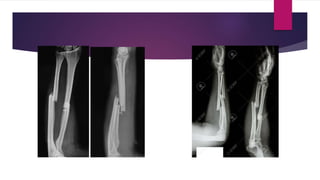

FRACTURE OF THE ULNAR SHAFT AND DISLOCATION OF THE PROXIMAL

RADIOULNAR JOINT (MONTEGGIA FRACTURE-DISLOCATION)

 An angulated fracture of the proximal half of the ulna is invariably accompanied by a

dislocation of the proximal radioulnar joint

 Thus, radiographic examination for fractures in the forearm should always include both the

wrist and elbow joints to avoid overlooking a fracture-dislocation

 In the common (extension) type of Monteggia fracture-dislocation, a hyperextension and

pronation injury produces a fracture of the proximal half of the ulna with anterior angulation

and anterior dislocation of the proximal radioulnar joint. This injury can also be produced by a

direct blow over the ulnar border of the forearm

 A rare variation of Monteggia fracture-dislocation is the flexion type, which is caused by a

flexion injury and characterized by posterior angulation of the fractured ulna and posterior

 Monteggia fracture-dislocations in adults are best treated by open reduction of the ulna so that its length

and alignment may be perfectly restored

 Internal fixation of the fracture should be obtained by means of either a compression plate and screws or

an intramedullary nail

 Correction of the ulnar deformity usually results in a closed reduction of the radial head, in which case it

is unnecessary to perform an open reduction of the dislocated proximal radioulnar joint or to repair the

ruptured annular ligament

 The limb should be immobilized in an above-elbow cast with the forearm in supination for approximately

3 months

FRACTURE OF THEULNAR SHAFT AND DISLOCATION OF THE PROXIMAL RADIOULNAR JOINT (MONTEGGIA FRACTURE-DISLOCATION)  An angulated fracture of the proximal half of the ulna is invariably accompanied by a dislocation of the proximal radioulnar joint  Thus, radiographic examination for fractures in the forearm should always include both the wrist and elbow joints to avoid overlooking a fracture-dislocation

 In thecommon (extension) type of Monteggia fracture-dislocation, a hyperextension and pronation injury produces a fracture of the proximal half of the ulna with anterior angulation and anterior dislocation of the proximal radioulnar joint. This injury can also be produced by a direct blow over the ulnar border of the forearm  A rare variation of Monteggia fracture-dislocation is the flexion type, which is caused by a flexion injury and characterized by posterior angulation of the fractured ulna and posterior dislocation of the proximal radioulnar joint  This type of injury is treated using the same principles as the extension type of Monteggia fracture -dislocation

 Monteggia fracture-dislocationsin adults are best treated by open reduction of the ulna so that its length and alignment may be perfectly restored  Internal fixation of the fracture should be obtained by means of either a compression plate and screws or an intramedullary nail  Correction of the ulnar deformity usually results in a closed reduction of the radial head, in which case it is unnecessary to perform an open reduction of the dislocated proximal radioulnar joint or to repair the ruptured annular ligament  The limb should be immobilized in an above-elbow cast with the forearm in supination for approximately 3 months